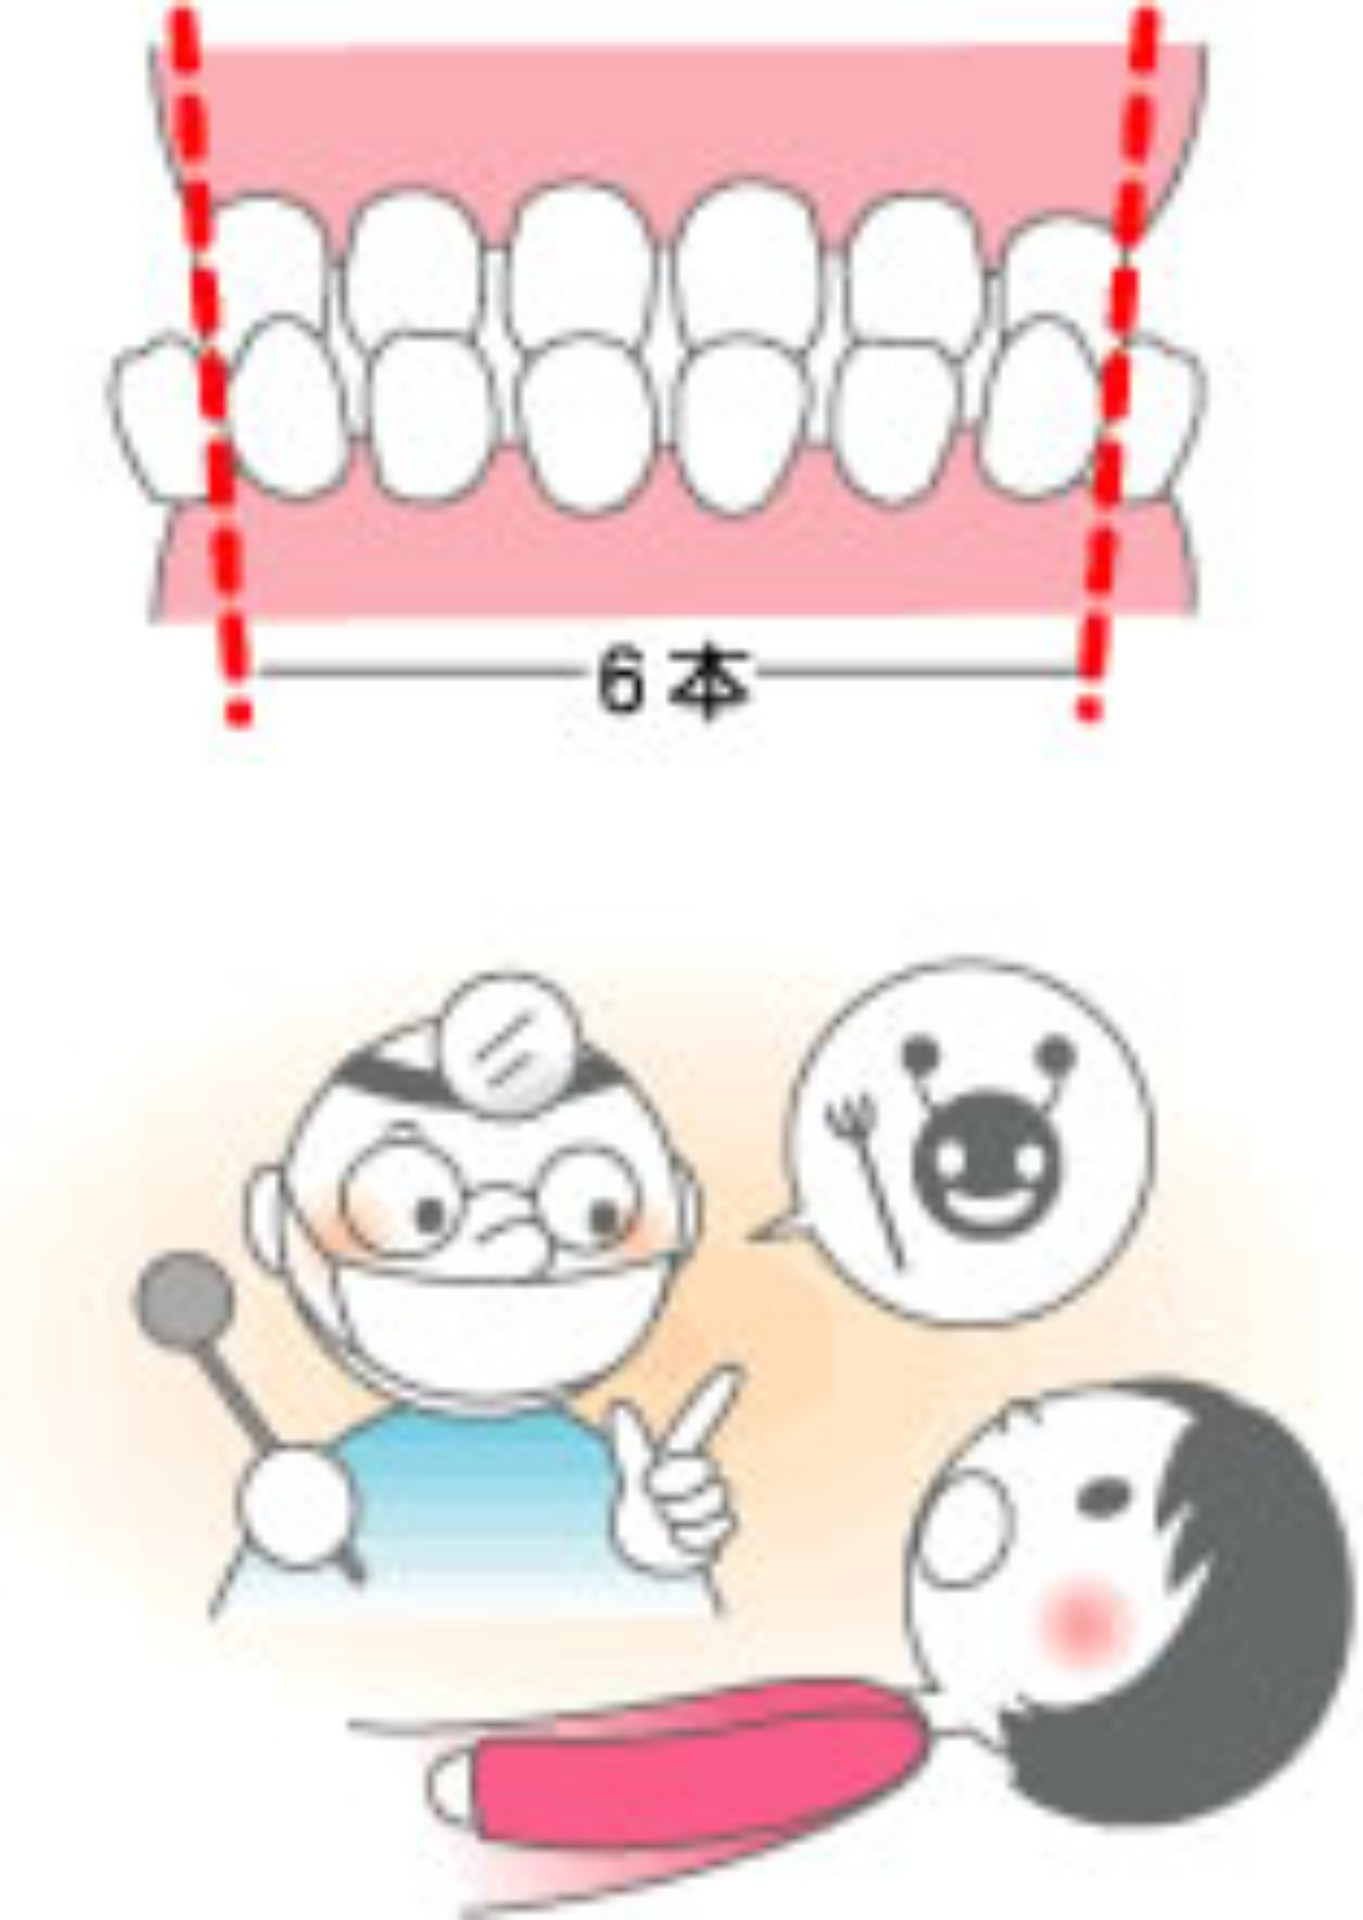

反対咬合はこうしてなる・こうして防ぐ

いわゆる「受け口」。 いわゆる「受け口」。

噛み合わせたとき、下の前歯が上の前歯より前に出ている噛み合わせです。

前に出ている下の前歯の数が4本以内なら自然に治る可能性がありますが、6本以上で骨格的に問題がある場合は、幼児期に骨格改善を目的とした矯正治療をしたほうがよいでしょう。